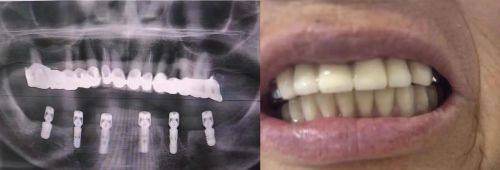

种植牙是一种现代口腔修复技术,打桩是种植牙过程中的关键步骤。打桩其实就是将人工牙根(种植体)植入牙槽骨内,就像给房子打下坚实的地基一样。种植体需要与牙槽骨紧密结合,形成稳定的结构,这样才能为后续安装牙冠提供有力的支撑。而牙冠则是种植牙的“表面工程”,它不仅能修复牙齿的外观,还能修复牙齿的咀嚼功能。

在放牙冠前,患者需要按照医生的要求定期复诊。复诊的目的是检查种植体与牙槽骨的结合情况,医生会通过X光等检查手段来判断是否可以安装牙冠。患者要严格遵守复诊时间,不要自行提前或推迟复诊。